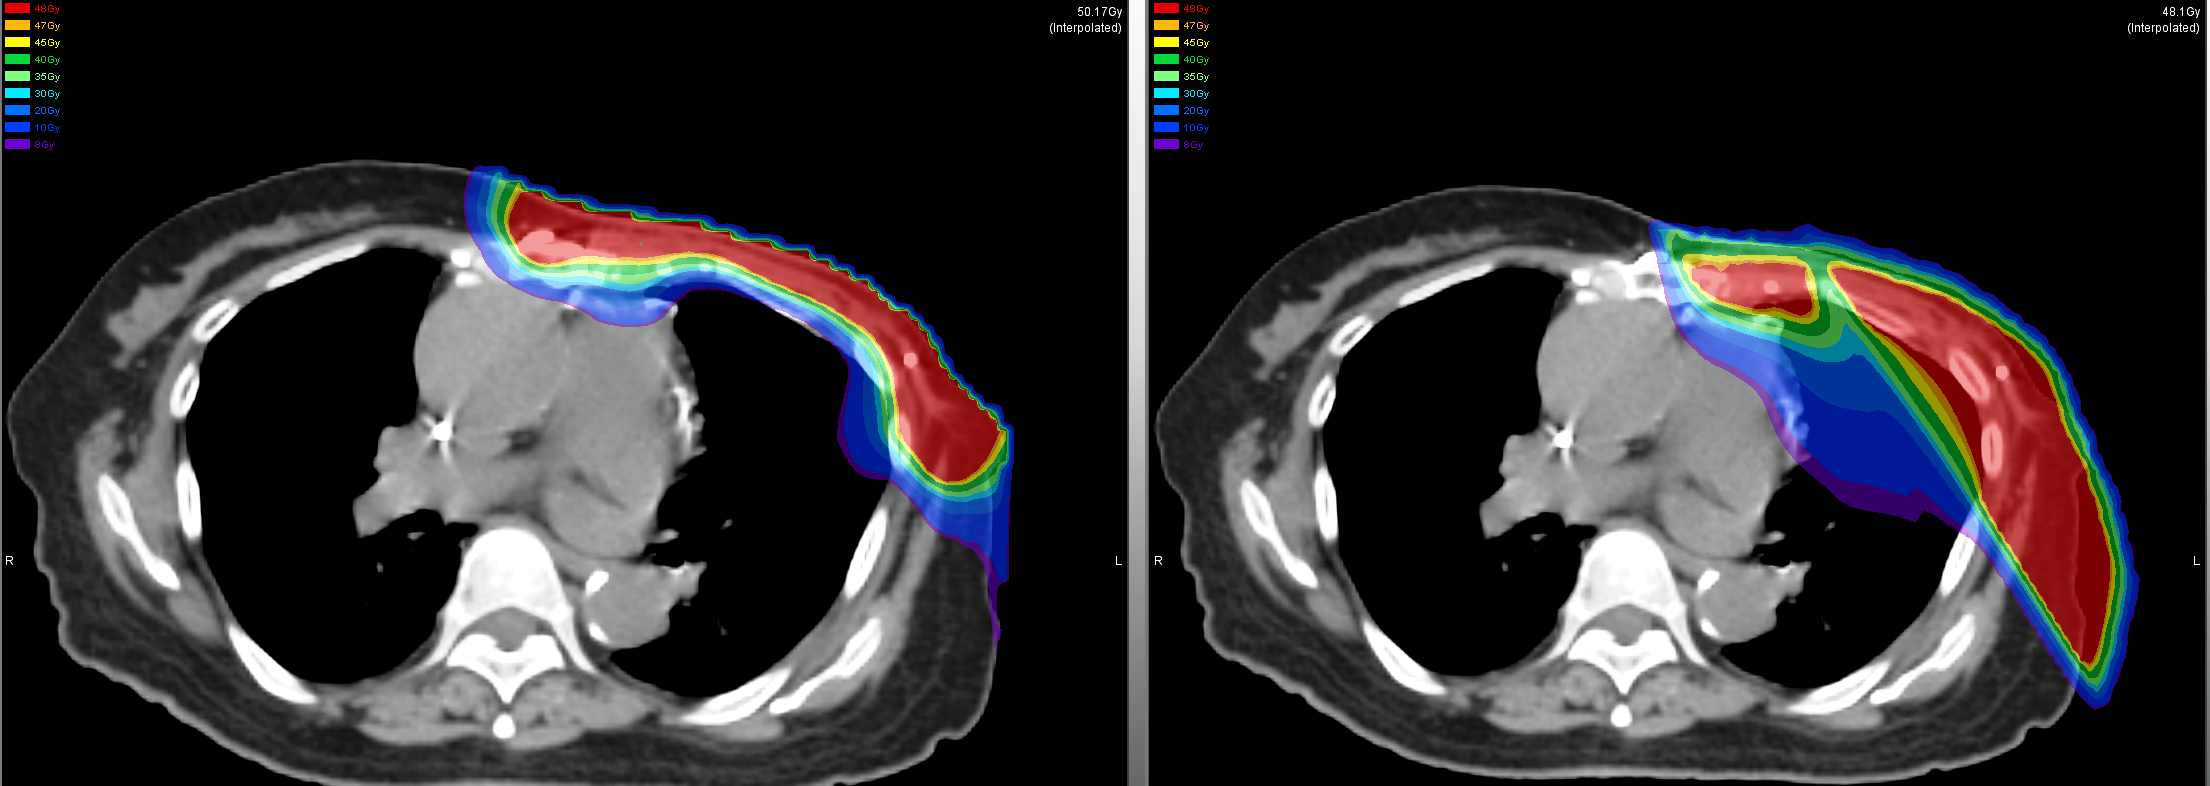

Radioterapia e zvogëlon rrezikun e përsëritjes së sëmundjes (recidivimit) në pjesët e ngelura të gjirit ose në nodet limfatike. Zbatohet, pra për qëllime shërimi – zakonisht pas kirurgjisë kursyese të gjirit (kur nuk hiqet i tërë gjiri) ose pas mastektomisë. Rrezatohen vetëm pjesë të caktuara.

Radioterapia zbatohet çdo ditë (pesë ditë në javë me pushim gjatë vikendit) gjatë 3 javësh ose metoda tjetër është zbatimi çdo të dytën ditë brenda 5 javësh. Një trajtim (fraksion i rrezatimit) zgjat disa minuta dhe nuk jep çrregullime gjatë procedurës.